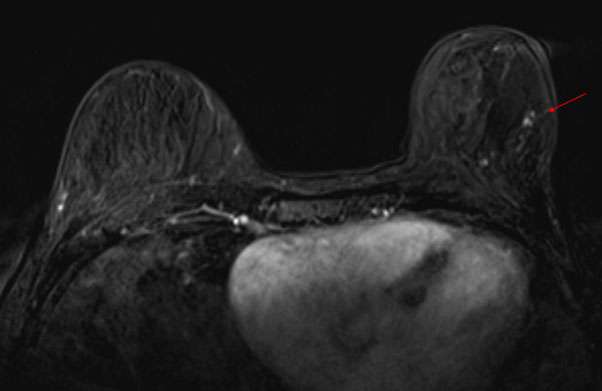

Breast MRI is highly sensitive for the detection of breast cancer and may be used in patients with Paget’s disease of the breast to establish the extent of disease. MRI may show thickening of the nipple/areola, asymmetric abnormal enhancement of the nipple/areola, enhancing masses, and linear/segmental non-mass enhancement.